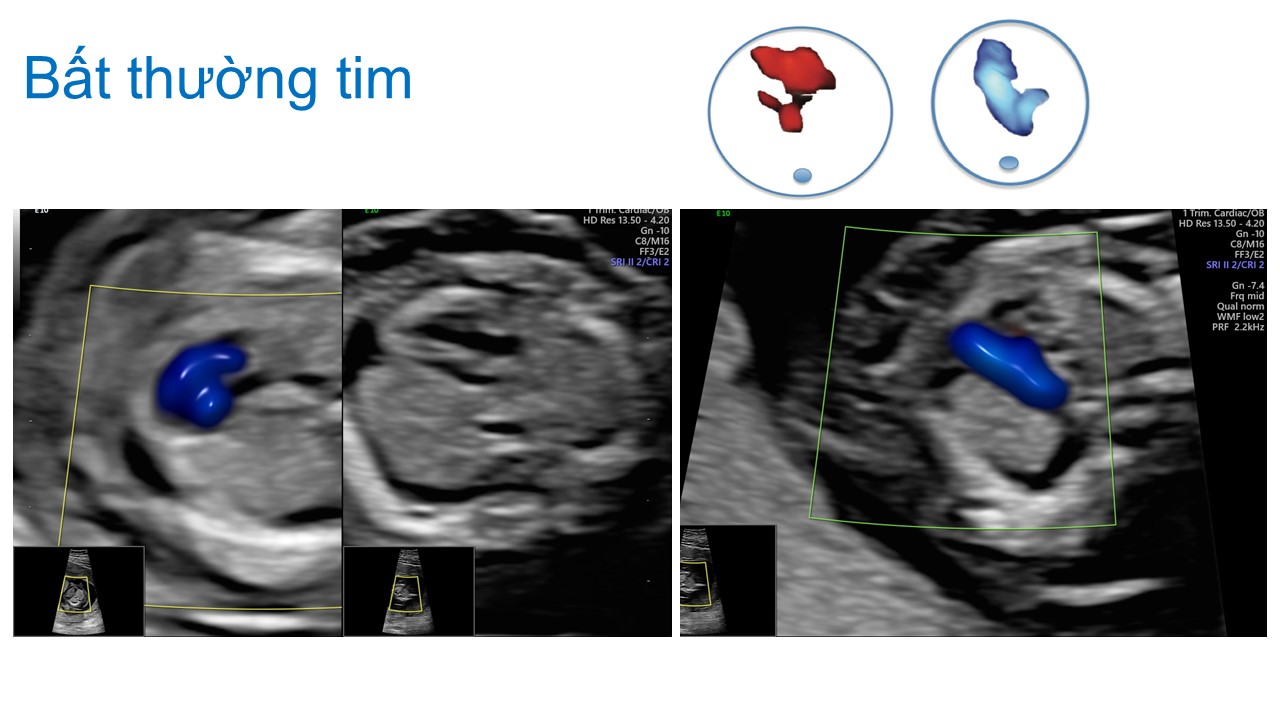

Siêu âm hình thai học quý I

Từ khóa: Siêu âm hình thai học quý I